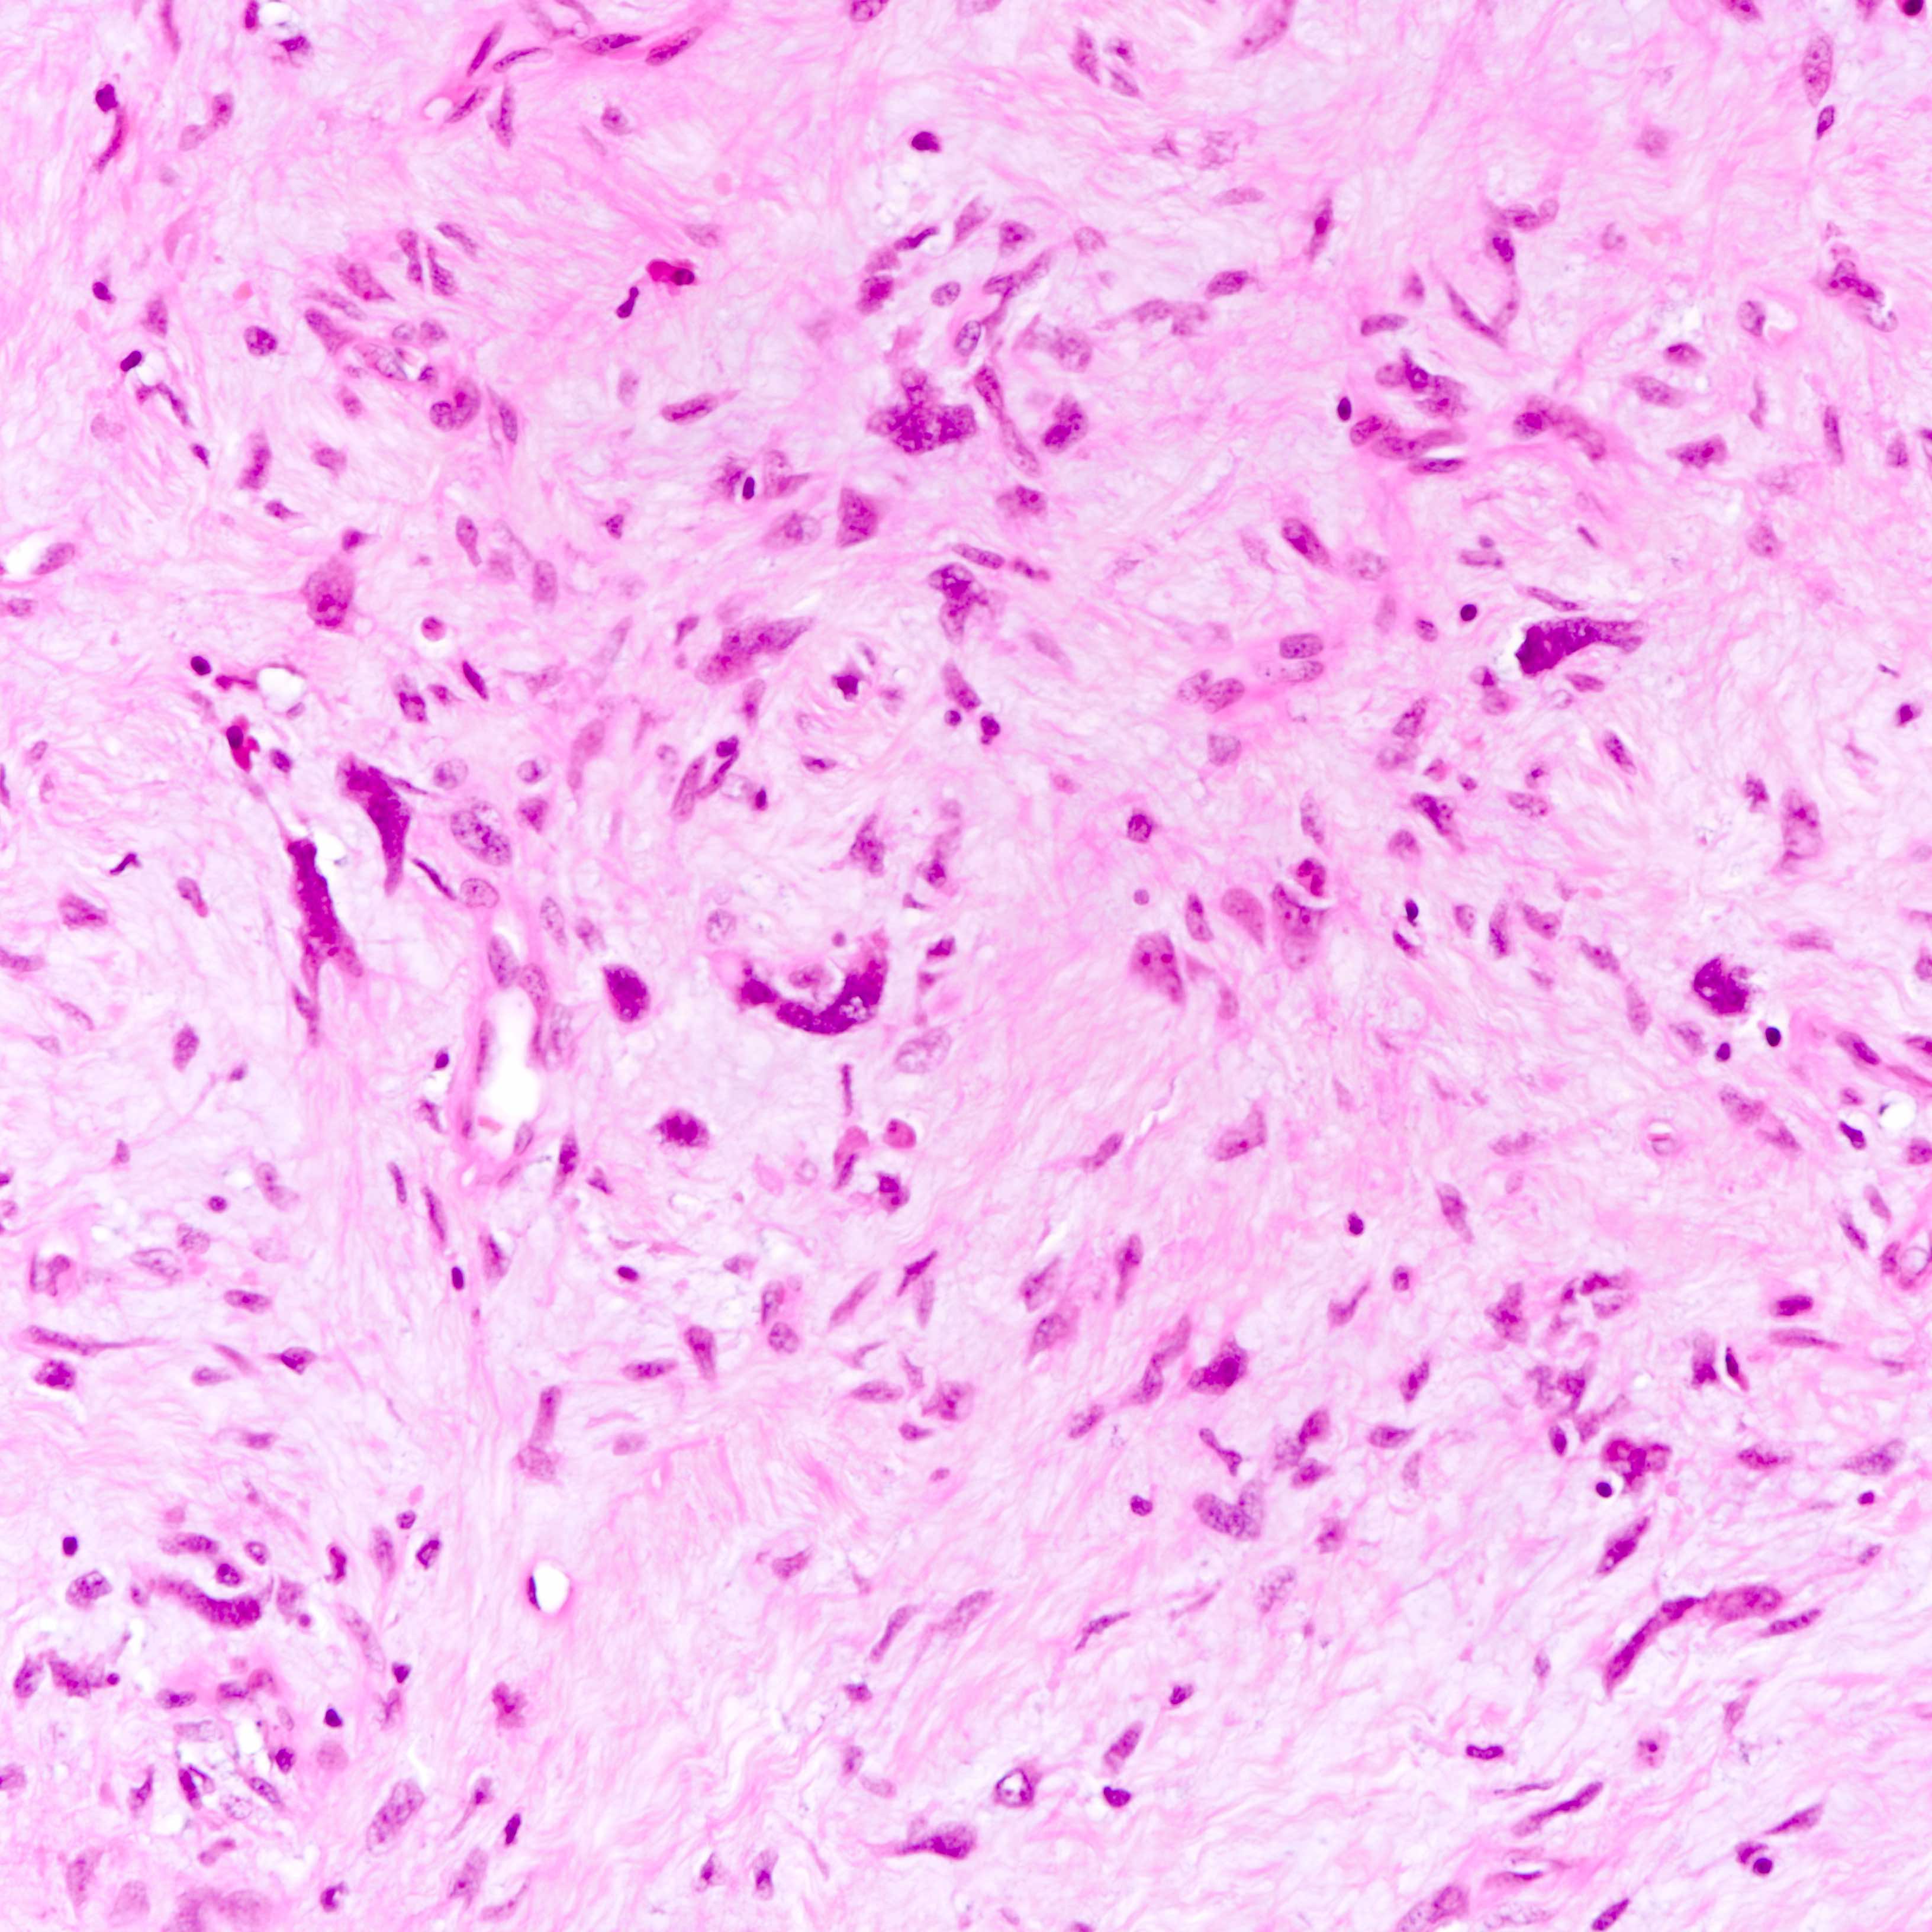

Microscopic (histologic) images

Contributed by Joshua J.X. Li, M.B.Ch.B. and Gary M. Tse, M.B.B.S.

Benign phyllodes tumor